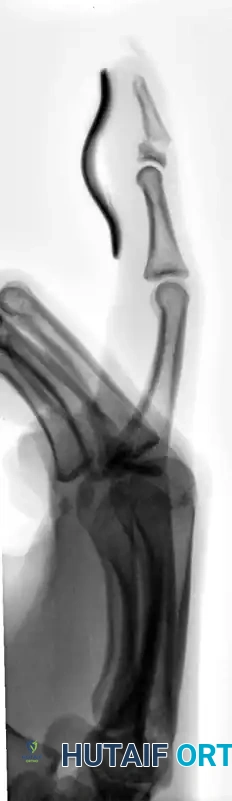

Management: Treatment is almost exclusively nonoperative. Continuous DIP joint extension splinting using a molded polythene (Stack) or aluminum splint is required for 6 to 8 weeks.

FIGURE 67-65 B: Aluminum splint achieving full extension of the distal interphalangeal joint.

Surgical Warning: When applying volar or dorsal splints, extreme care must be taken to prevent skin maceration and ulceration. Hyperextension of the DIP joint must be strictly avoided; it causes blanching of the dorsal skin, leading to ischemia and subsequent full-thickness skin breakdown over the joint.